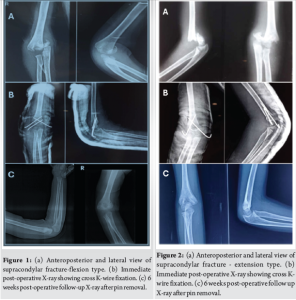

A total of 35 pediatric patients, aged between 2 and 12 years (mean age: 7.15 years), underwent supracondylar pinning for the supracondylar humerus fractures. Of these, 22 were male and 13 were female. In the study, 21 cases involved the left side, while 14 cases affected the right side. Extension-type fractures were observed in 93% of patients, while 7% had flexion-type fractures. All patients were followed up for a minimum of 6 months. Superficial pin tract infections developed in 10 patients, all of whom recovered after pin removal and oral antibiotics treatment. No cases of severe infection or septic arthritis were reported. Cubitus rectus seen in 3 patients (8%) who showed positive functional outcomes during the follow-up. No instances of neurovascular injury, compartment syndrome, and migration of the pin were observed in this study. At the 6-month follow-up, the mean Mayo Elbow score was 96.01 ± 2.80. Based on this assessment, 31 patients achieved excellent outcomes, while 3 had good outcomes and 1 had fair outcome. No poor outcomes were recorded. The mean Baumanns angle was 75.90 ± 10.01 (Fig. 1-4].

Supracondylar humerus fractures are one of the most common fractures that affect children. It constitutes for more than 50% of elbow fractures. The fractures typically occur within the first 10 years of life and affect the distal humerus, near the metaphysis. It is of two types – flexion and extension type [6]. The standard treatment involves closed reduction followed by percutaneous pin fixation. Several treatment methods have been used in the management of supracondylar humerus fractures. Non-surgical treatment is generally considered only for fractures that are not displaced or displaced minimally. They are managed with reduction and stabilized with a POP cast. However, in cases of displaced or open fractures, surgical intervention is necessary to prevent complications, such as malunion, cubitus varus, restricted elbow movement, and persistent pain. Open reduction with fixation is recommended in specific scenarios, such as open fractures requiring vascular exploration or fractures that cannot be reduced by closed methods. In this study, the average age of the children was 7.15 years, ranging from 2 to 12 years. A study conducted in Saudi Arabia by Khan et al. reported a similar mean age of 8.1 years [7]. The majority of our study population was between 5 and 10 years (62%), which is consistent with the findings by Fowels et al. According to Reising et al., supracondylar humerus fractures were common for the ages above 4 years and below 9 years [8]. This study also found that boys were more frequently affected than girls (62.8% vs. 37.2%), a trend that aligns with findings by Devkota et al., who reported male–to-female ratio of 58:44. This difference is due to boys higher level of sports and physical exertion, making them more susceptible to falls and injuries [9]. Among 35 cases, 21 involved the left arm while 14 affected the right side. These findings correspond with those of Devkota et al., who reported a left-to-right arm ratio of 54:48. This pattern is often attributed to the protective function of the non-dominant limb during falls [9]. The clinical outcomes in this study were assessed using the Mayo Elbow score. At the 6 month follow-up, the mean score was 96.01 ± 2.80, which aligns with findings by Sinikumpu et al., who reported a mean score of 96.4 in patients with modified Gartlands type 3 fractures [10]. Similarly, Ulmar et al. documented excellent outcomes, reinforcing the effectiveness of the treatment approach used in this study [11]. On an anteroposterior radiograph, Baumanns angle is defined as the angle formed between the physeal line of the lateral condyle and the distal humeral metaphysis in relation to the long axis of the humerus. At 6 months, three patients showed cubitus rectus. The standard Baumanns angle ranges from 64° to 81°. In this study, the mean Baumanns angle at 6 months was 75.90 ± 10.01, which is within the acceptable range. Similar results were observed in a study by Lee et al., which found no significant changes [12]. In addition, Kitta et al. had used humeral capitellar angle to assess how the fracture fragments were reduced, and specifying the importance of maintaining the carrying angle. The mean humeral capitellar angle was 72.3 [13]. Basaran et al. conducted a similar study, reporting an insignificant difference between closed reduction with or without a medial incision [14].